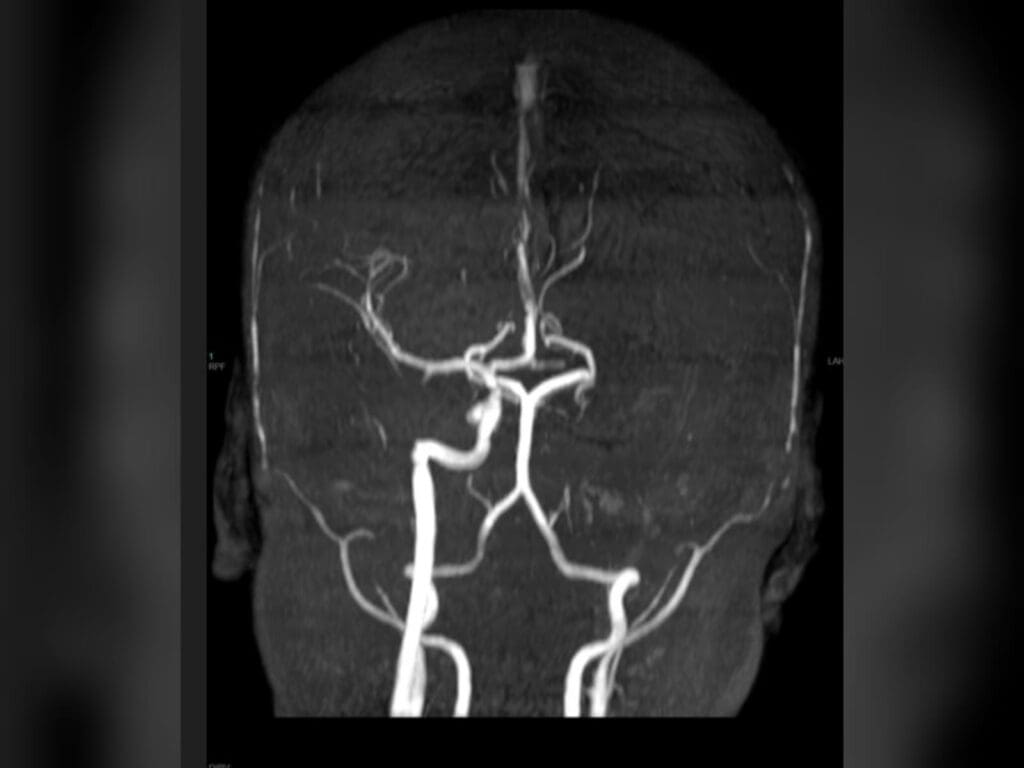

בשל הדחיפות, ד"ר אליאל בן דוד, מנהל היחידה לניורו-רדיולוגיה אבחנתית הוזעק לחדר הבדיקה ואבחן תוך כדי בדיקת ה-MRI חסימה משמעותית של אחד מעורקי המוח הראשיים.

במהלך הצנתור המורכב התברר כי עורק התרדמה הפנימי משמאל חסום ממוצאו. החסימה הייתה עקשנית ולא ניתנת לפתיחה בדרכים המקובלות בצנתורי שבץ. לבסוף הוחלט על השתלת תומכן (סטנט) באיזור החסימה בעורק במוח, מה שאפשר הוצאת חלקי קרישי דם ופתיחת החסימה.